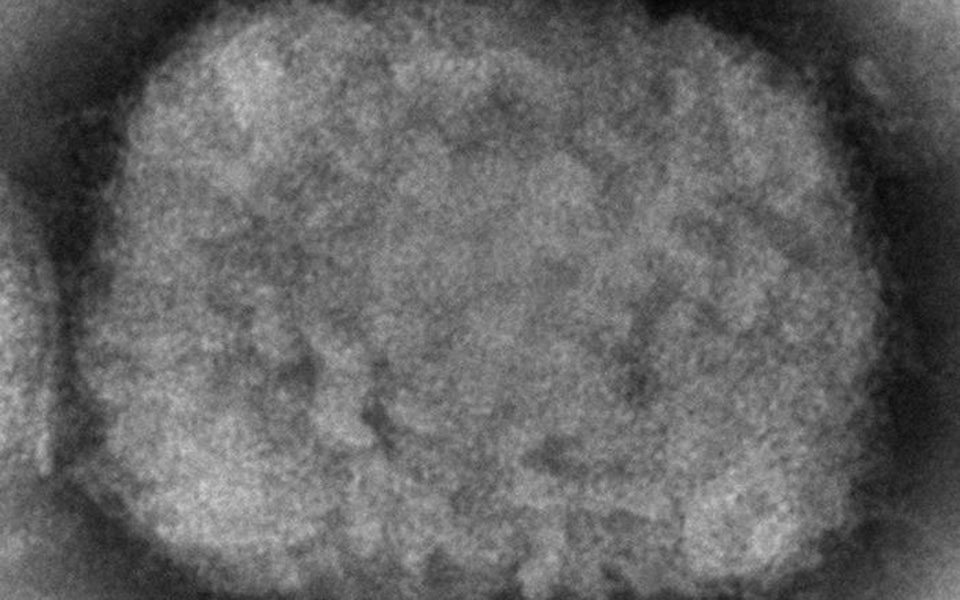

Στα εμβόλια και στις θεραπείες κατά της ευλογιάς των πιθήκων αναφέρθηκε ο καθηγητής Πολιτικής της Υγείας του LSE, Ηλίας Μόσιαλος.

Όπως σημείωσε, τα κρούσματα της ευλογιάς των πιθήκων είναι λιγότερα από 200 παγκοσμίως, παρόλα αυτά πολλοί ανησυχούν για την ύπαρξη και την διαθεσιμότητα φαρμάκων και εμβολίων γι’ αυτή τη νόσο. Όμως υπάρχουν διαθέσιμα φάρμακα και εμβόλια.